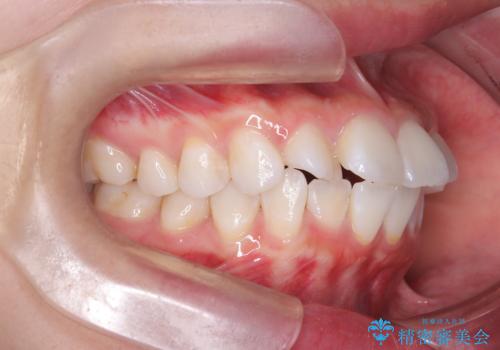

突き出た前歯を下げて理想的な横顔に。上下左右4番抜歯による審美ワイヤー矯正

精密検査の結果、歯を後方へ下げるためのスペースが不足していたため、上下左右の4番目の歯(第一小臼歯)を計4本抜歯する計画を立案しました。抜歯によってできたスペースを最大限に活用し、前歯を後ろに下げることで、口元のボリュームを抑え、バランスの良いEライン(横顔のライン)を目指すこととしました。装置は、日常生活で目立ちにくい審美ワイヤーを選択しました。

治療は、審美ワイヤーを用いて抜歯スペースを徐々に閉じながら、前歯の角度と位置を精密にコントロールして進められました。ワイヤー矯正は歯を三次元的にしっかりと動かすことができるため、前歯を単に倒すのではなく、根元から理想的な位置へと誘導しました。

1年半の治療期間を経て、抜歯したスペースは完全に閉じ、突き出ていた前歯はすっきりと内側に収まりました。噛み合わせの精度も向上し、機能面でも良好な結果が得られています。